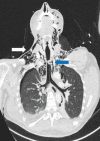

Tracheobronchial injury (TBI) is a rare life-threatening injury that can result from either penetrating or blunt trauma. Treatment may be surgical or conservative, but the evidence regarding which is the best approach is still very scarce. This case report describes the successful conservative management of a 32-year-old male with a traumatic tracheal laceration. The alarming signs and symptoms, the imaging modalities of choice, the rationale behind the treatment strategy, and the most common complications are detailed here. Through this case, the authors wish to highlight the features that should lead to the suspicion of this potentially fatal traumatic injury, as well as raise awareness on how to adequately manage these patients.